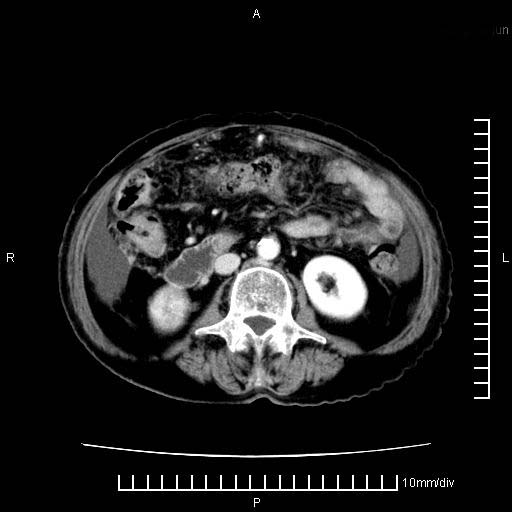

上腹疼痛月余,外院核磁诊断胰腺癌。现临床示右下腹可明显触及包块,可片子上怎么没有看到?

1.胰腺颈体部癌。

2。腹腔积液。

3。右胸腔积液,伴右肺下叶部分萎陷。

4。右肾盂囊肿。

胰腺体部癌累及周围器官,腹膜、粘连

1。胰腺ca伴腹膜腔转移

2。肝左叶低密度灶,考虑转移可能

胰腺体部癌累及周围器官,腹膜、粘连,临床摸到的可能是粘的组织

胰腺结构模糊,胰尾部见囊性包块,周围脂肪密度增高,左肾前筋膜增厚,胸水、腹水。不符合胰腺ca伴腹膜腔转移。考虑胰腺炎伴假性囊肿形成、胸腹腔积液。

右肾盂囊肿。

1)考虑胰腺癌并胰腺假性囊肿形成。2)肝内低密度灶,不排除转移。3)右肾盂积水。4)腹水。5)右侧胸腔积液并右肺下叶部分膨胀不全。